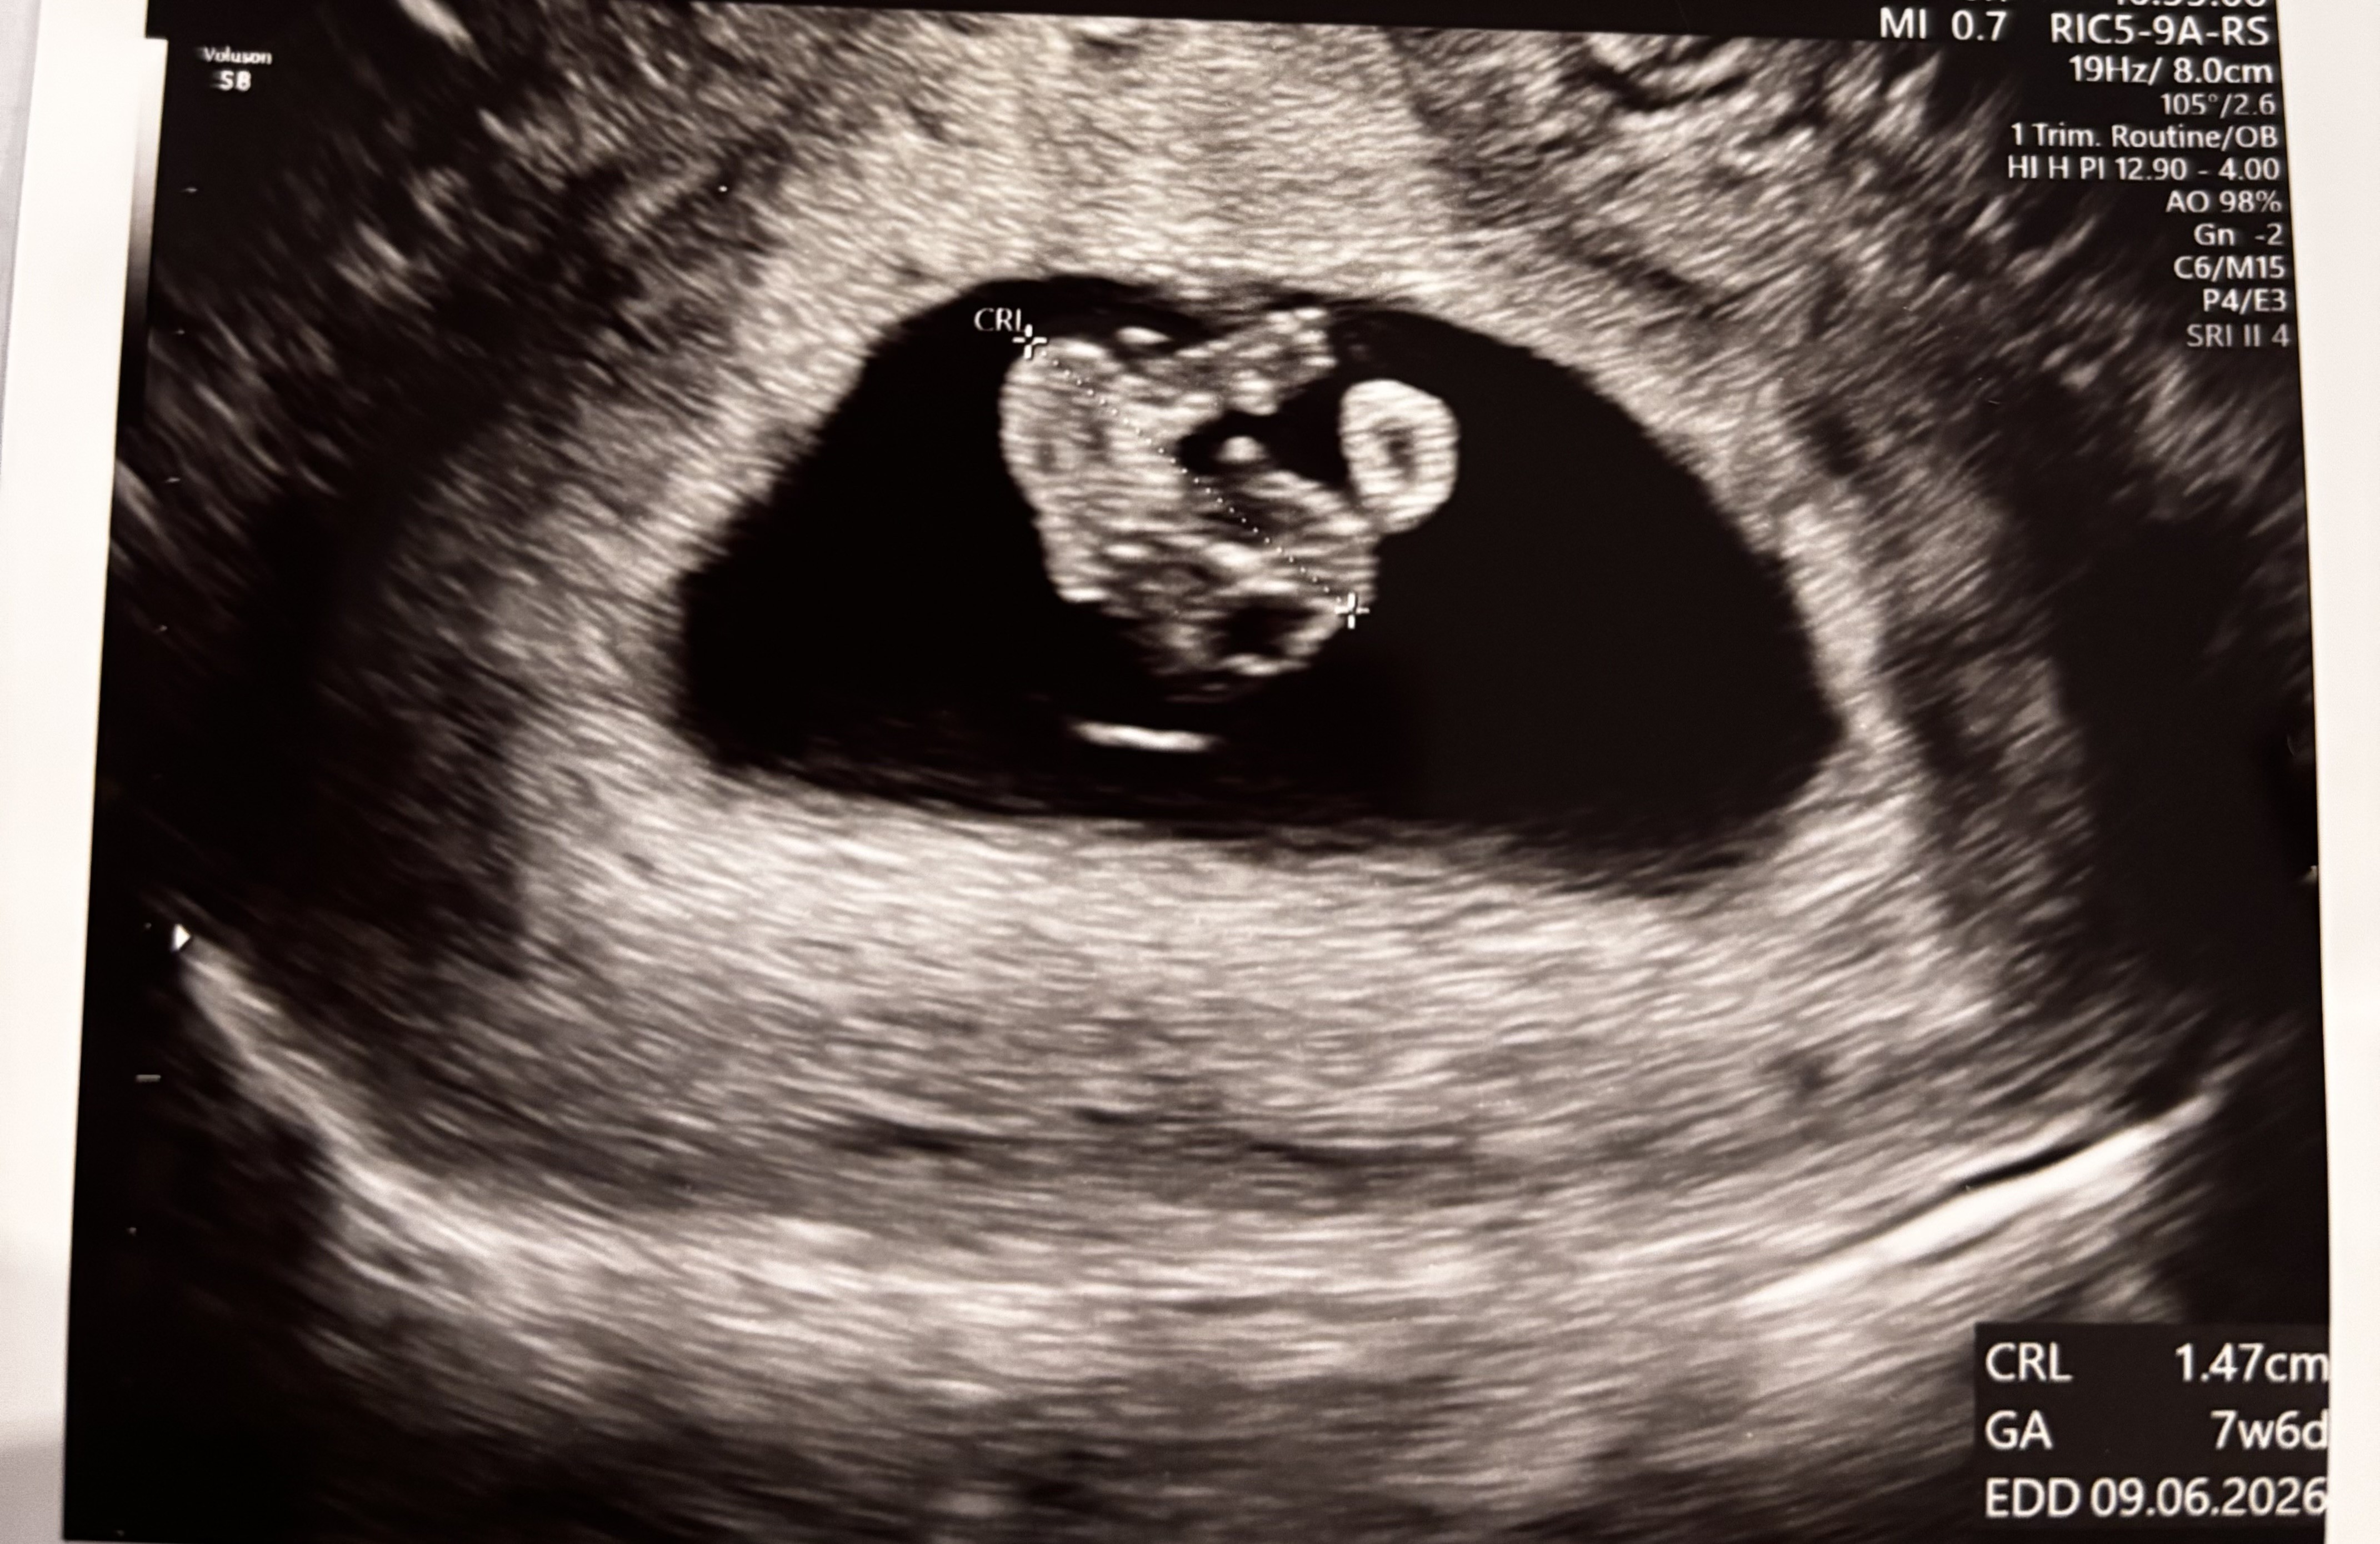

cześć dziewczyny, również już jestem po wizycie. Oczywiście było opóźnienie, idzie się przyzwyczaić. Słyszeliśmy dzisiaj przez chwilę serduszko, bije 163 bpm- także idealnie, fasolka w porównaniu z tym co było półtora tygodnia temu jest ogromna 😍 kolejna wizyta za dwa tyg, uzgodniliśmy że na początku będziemy się widywać częściej, dostałam również już skierowanie na prenatalne badania ❤️

Załączniki

• IMG_7566.jpeg

IMG_7566.jpeg

1,4 MB · Wyświetleń: 60